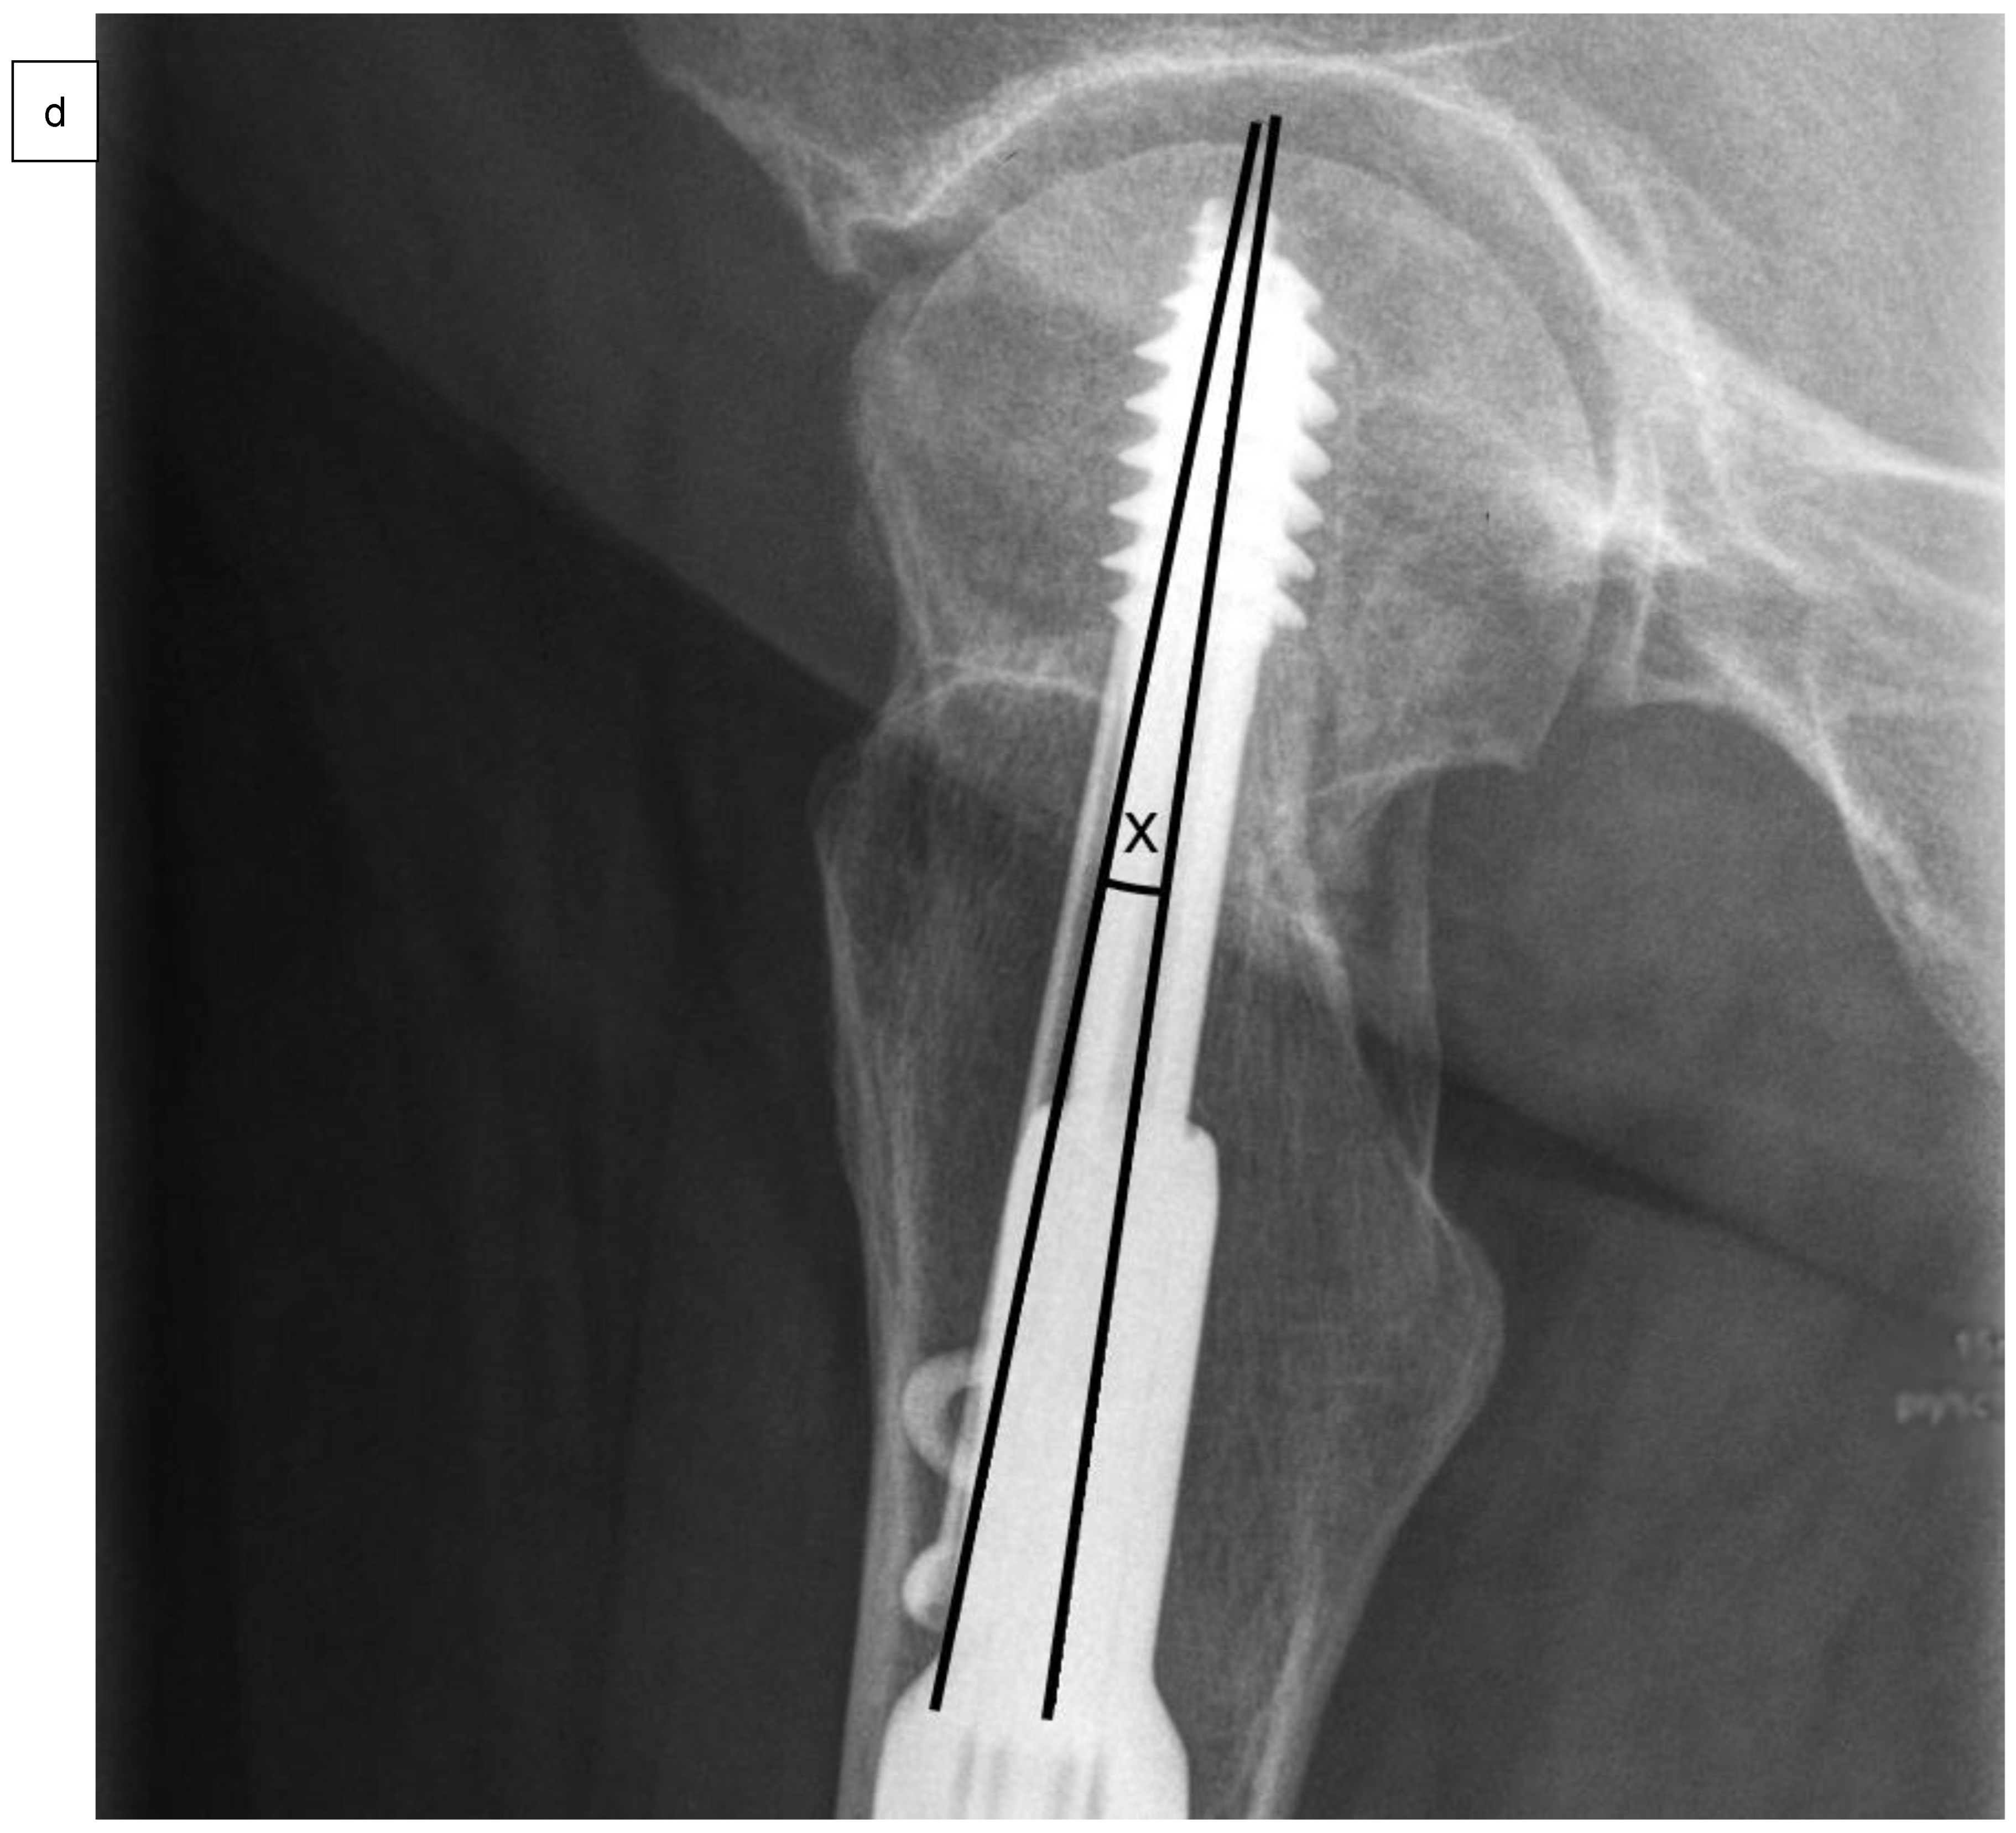

| Angle between SHS and ARS in frontal plane | 0.0 ± 0.2° | 0.0 ± 0.3° | 0.56 |

| Angle between SHS and ARS in axial plane | 2.2 ± 1.8° | 2.4 ± 1.5° | 0.76 |